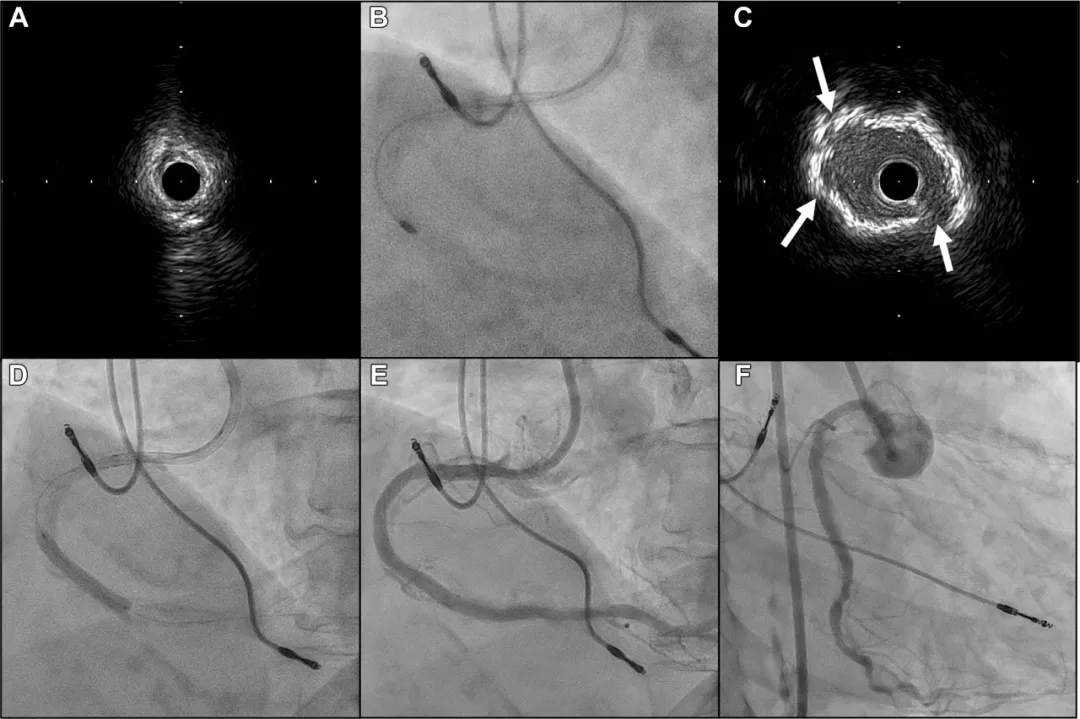

图2 二次手术冠状动脉造影及IVUS图像

(A)右冠状动脉中段仍存在严重狭窄。

(B)病变位于心室侧。

(C)残余真腔内的导丝位于钙化结节对侧,该导丝偏向不利于旋磨术及轨道旋磨术(白箭头指示导丝)。